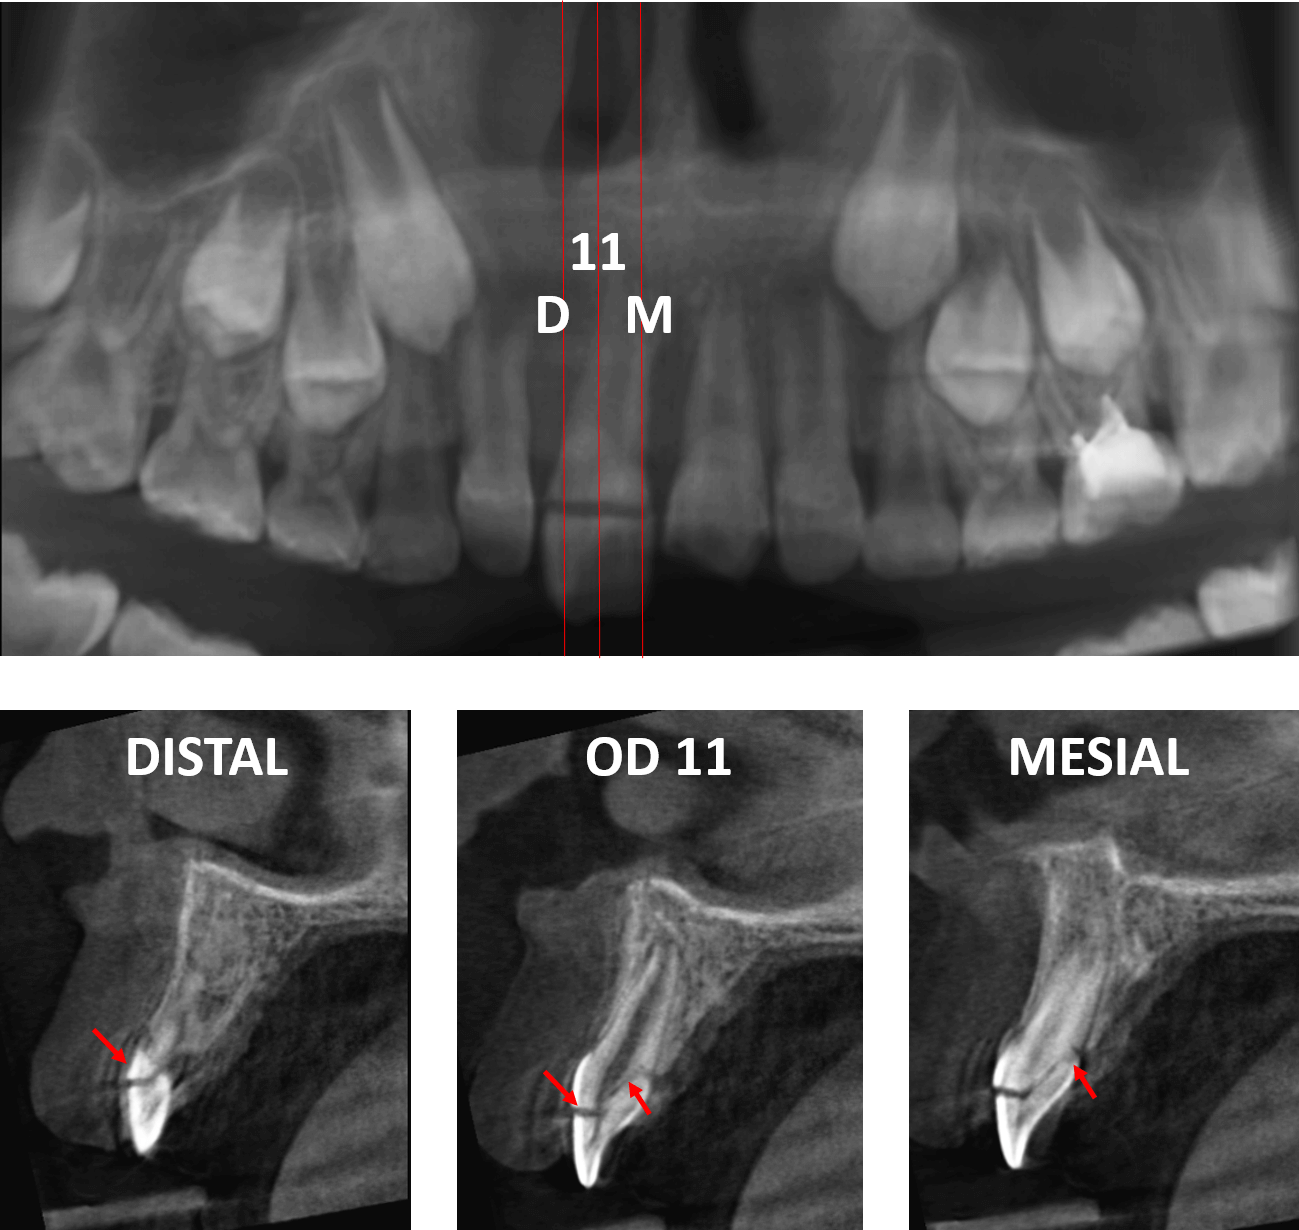

Fig.1

En la evaluación con tomografía computarizada cone beam, se realizó la reconstrucción panorámica de la zona anterior del maxilar superior y los cortes transaxiales del órgano dentario 11 (Fig.1) el cual se observa una fractura horizontal coronaria a nivel del tercio medio por vestibular comprometiendo la pulpa dentaria, siguiendo su trayecto de forma oblicua hacia la superficie cervical por palatino.